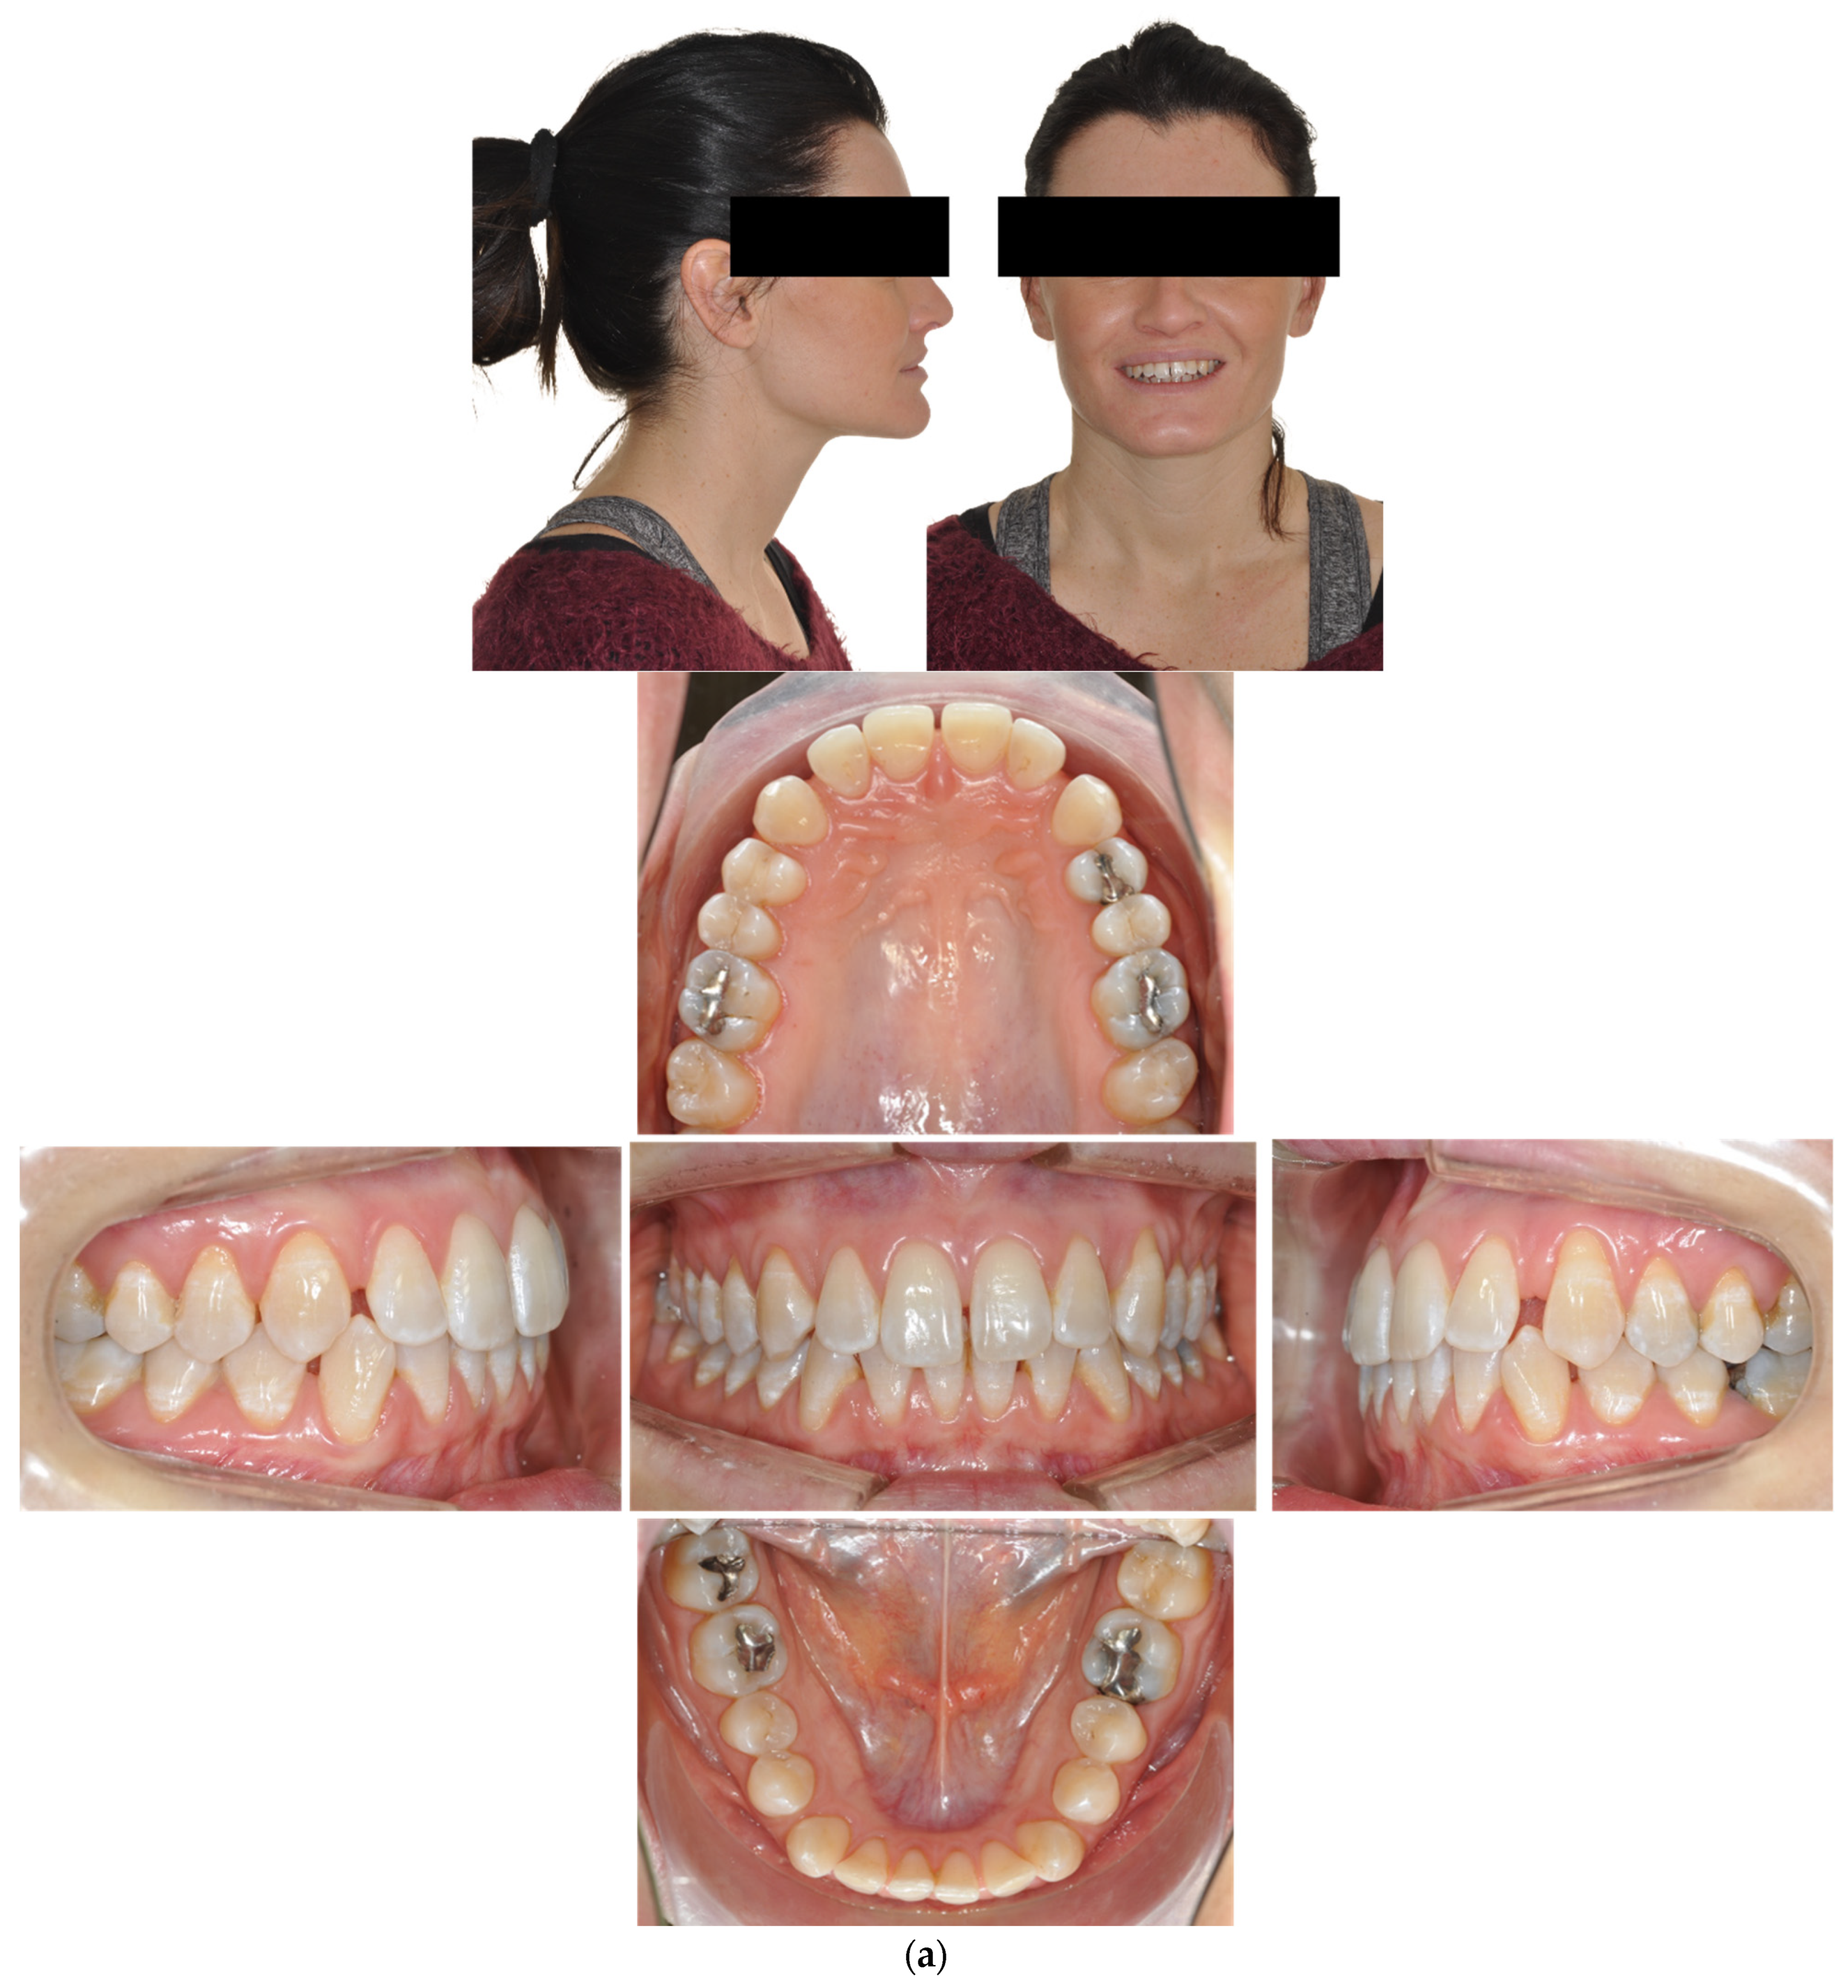

4.3. Case 3: Class II Subdivision with a Deep Bite